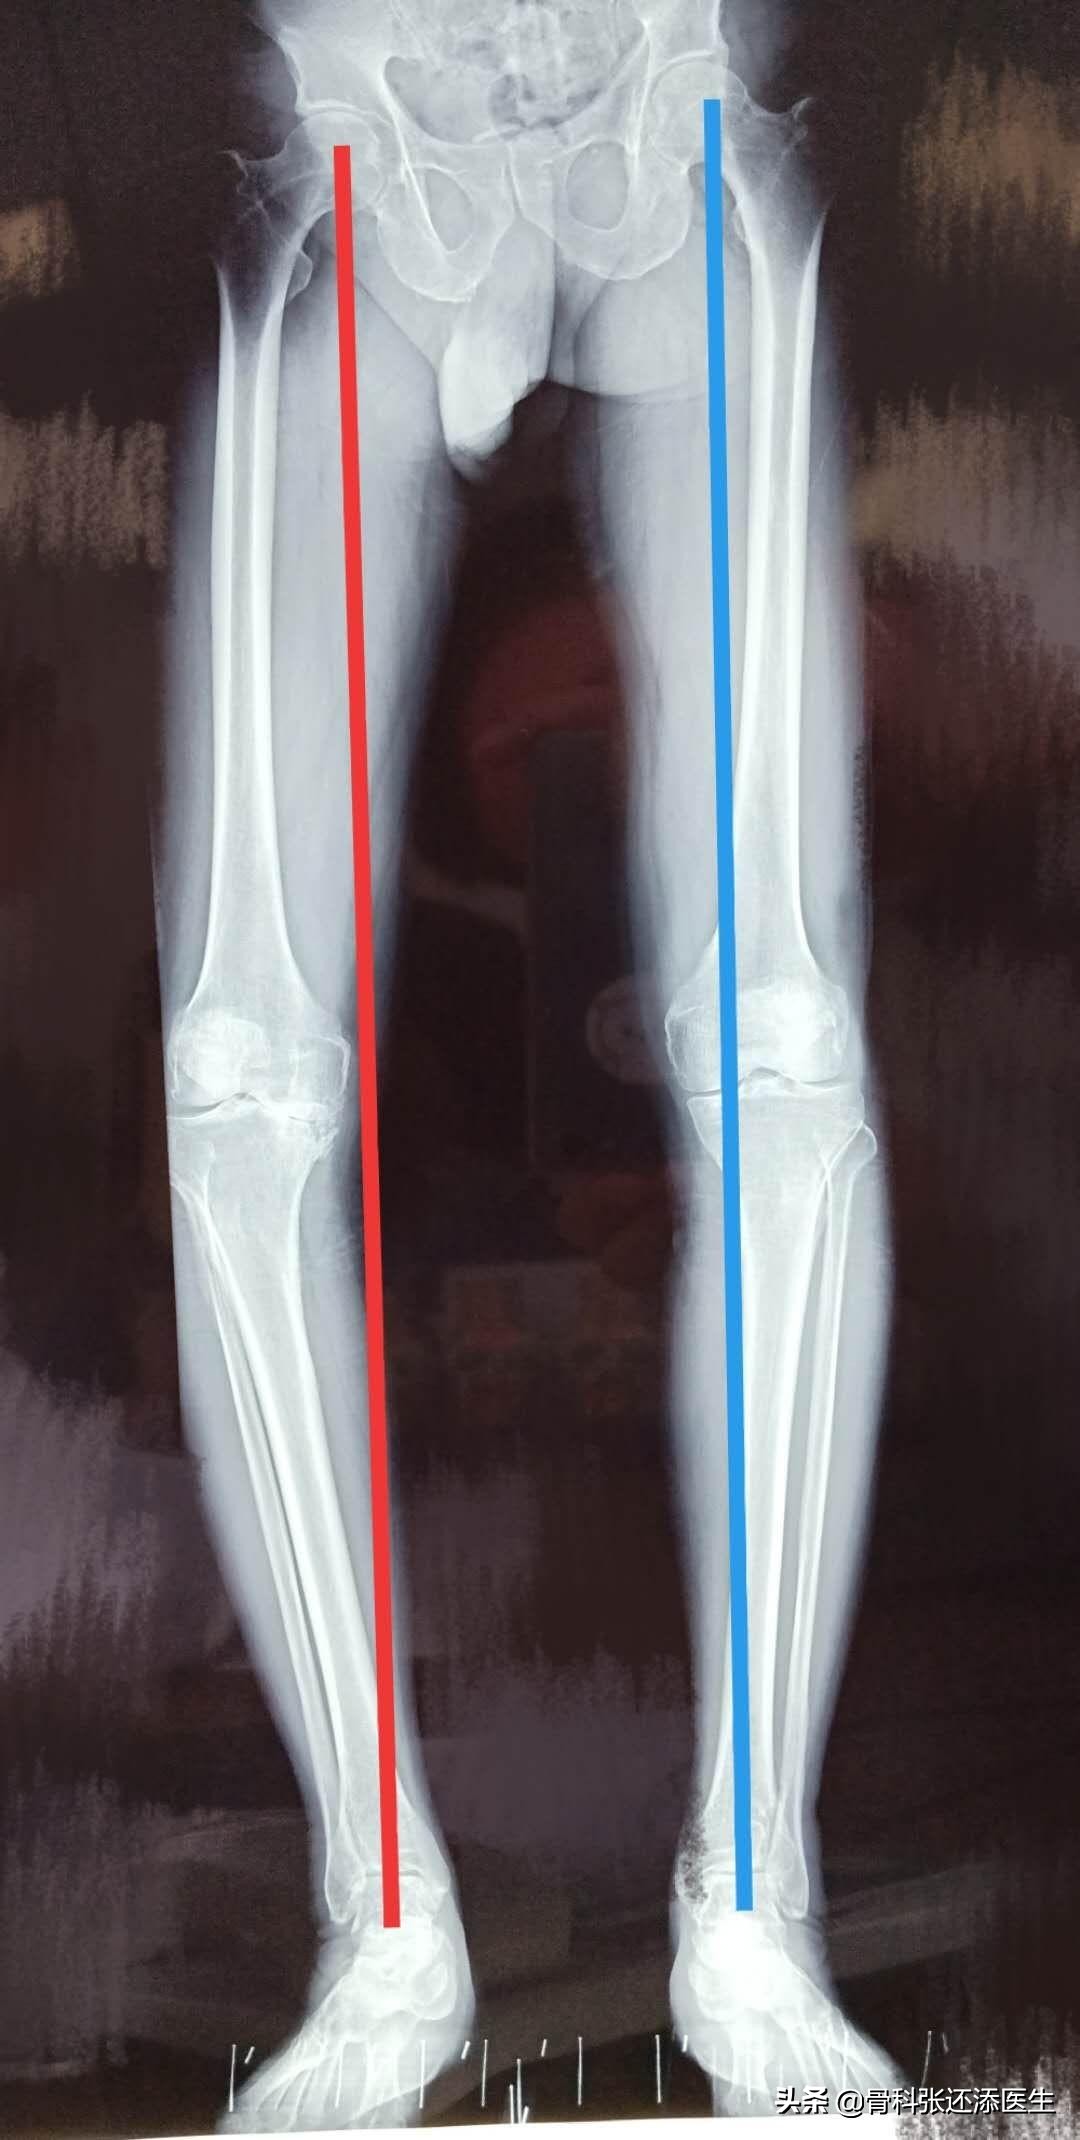

所以,对于一个骨关节炎而关节弹响的患者,首先可以照个双下肢站立位的全长X光片,通过判断膝关节的中心是否在髋关节中心及踝关节中心的连线上而掌握下肢力线是否正常。假如膝关节的中心在连线的外侧,则是膝关节内翻。反之,则是膝外翻。

看一个实际的病例,蓝线显示,膝关节的力线勉强连接髋关节,膝关节和踝关节;但是,红线已经严重偏离,进一步检查,此侧膝关节已经完全烂掉,只能一瘸一拐行走。

力线

所以年纪比较大的朋友,出现膝盖疼痛及活动时总发生响声时,可以要到关节外科照一个X光,最好是双下肢站立位的全场片,能够看到膝关节的力线和磨损情况。轻度的,行保守治疗(注射透明酸钠,口服软骨补充剂,功能康复锻炼等),重度患者,需要进行全膝关节成形术。